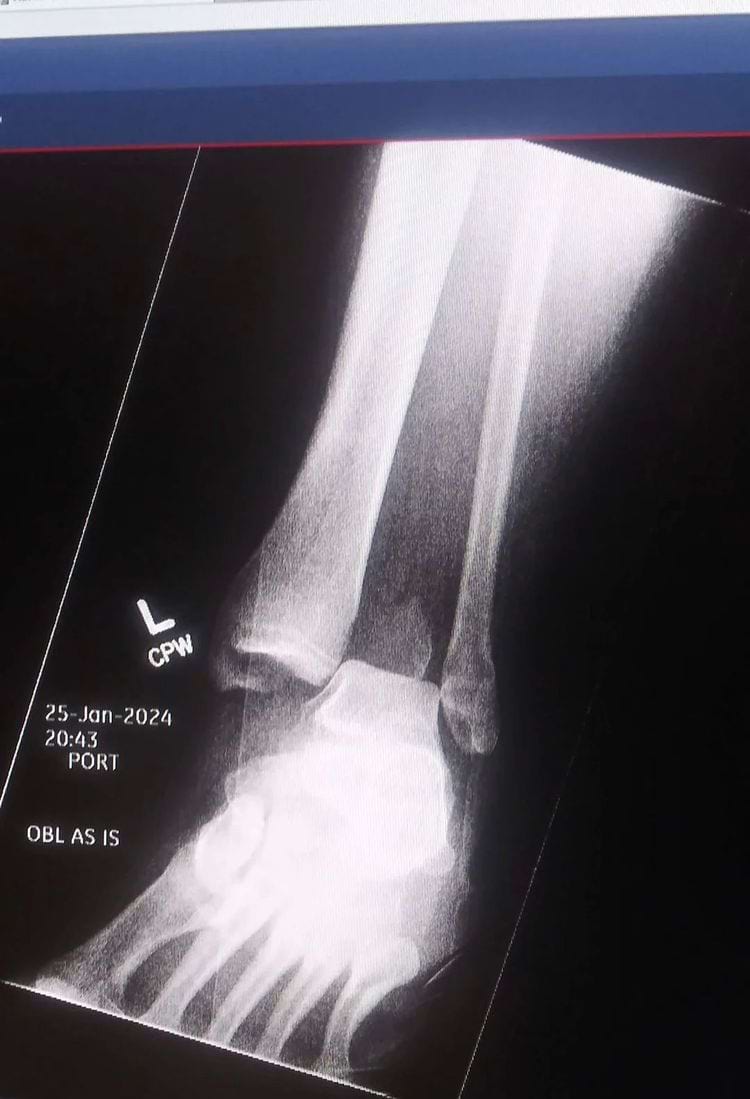

Рентген сломанной лодыжки, на которой кости ног пациента напоминают палочки для еды